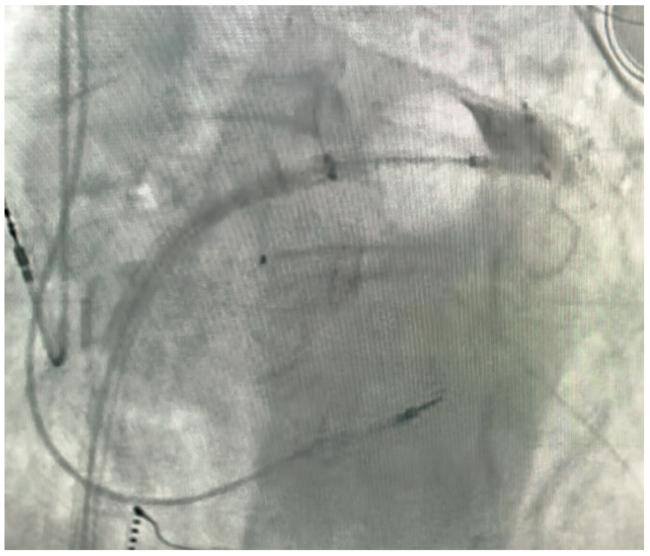

Pulmonary vein isolation (PVI) using cryoballoon (CB) ablation is an established therapy for treatment of patients with symptomatic paroxysmal and early persistent atrial fibrillation (AF).1,2 Complete PV occlusion with the CB ablation catheter is recommended prior to freezing to achieve successful PVI. CB ablation, as it was first described in 2005, required the use of an intravenous (IV) contrast injection through the central lumen of the CB catheter to verify complete PVI with the balloon catheter.3 To this day, most electrophysiology labs, including our lab at St. Anthony’s Hospital in Lakewood, Colorado, use IV contrast injection under fluoroscopy as the standard of care to confirm complete PVI prior to delivery of CB ablation therapy (Figure 1, Video 1).

Video 1. Fluoroscopic view of the CB ablation catheter advancing to PV ostium, followed by IV contrast injection and demonstrating complete PV occlusion.